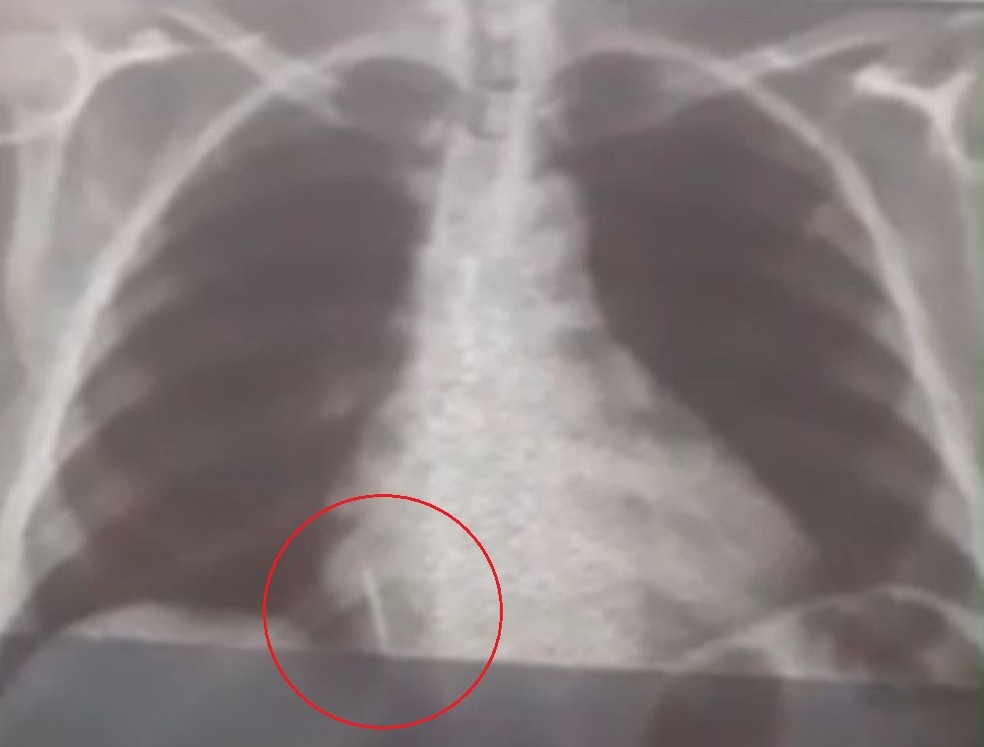

Iolanda Mariano de Melo Simplício está com o material alojado no pulmão deste então. O filho dela conta que a mãe sente muitas dores e já perdeu cerca de 10 quilos desde o ocorrido.

“A Secretaria Municipal de Saúde nos deu assistência para a realização dos exames. A gente foi para Natal inúmeras vezes com ela para fazer tomografia, raio-x, hemograma, risco cirúrgico, mas até agora nada. Já são quase 29 dias e praticamente não temos resposta. A gente quer uma solução, porque é um corpo estranho que está dentro do pulmão dela”, conta Rohnhalyson Mariano.